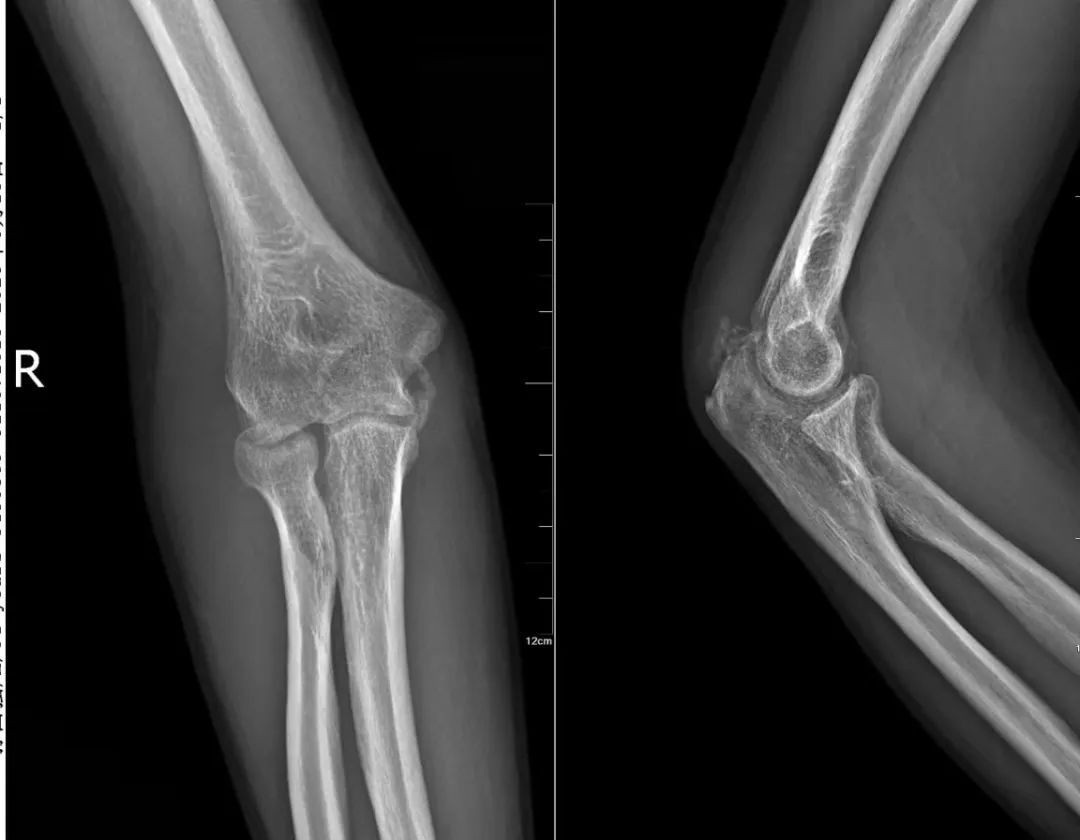

34岁的孙先生对此深有体会:半年前一次摔伤导致右侧桡骨头骨折,在当地成人ai 石膏固定3周后,右肘关节竟逐渐“冻结”,伸屈旋转严重受限。虽经康复治疗,改善甚微。

多方求医后,孙先生找到国内肩肘外科领域专家、成人ai 执行院长查晔军。经详细检查,确诊为“创伤后肘关节僵硬”。

考虑到孙先生僵硬的严重程度和病程已达6个月,院长查晔军团队决定施行关节镜辅助下微创肘关节松解术。

肘关节结构复杂,神经血管密布如“雷区”,关节间隙极为狭小,这使肘关节镜手术成为骨科领域极具挑战性的精细操作。